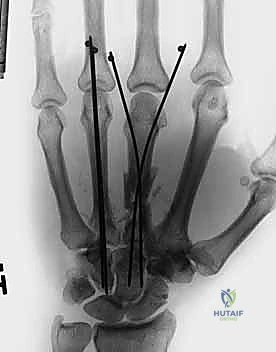

1. التثبيت باستخدام الأسلاك الدقيقة (K-wires)

تُعد هذه الطريقة (Percutaneous Pinning) من التقنيات طفيفة التوغل. يتم إدخال أسلاك معدنية رفيعة جداً عبر الجلد لتثبيت العظم المكسور تحت توجيه الأشعة السينية المستمرة (C-arm) داخل غرفة العمليات.

* الميزة: جروح صغيرة جداً، تعافٍ أسرع للأنسجة الرخوة.

* الإزالة: غالباً ما يتم إزالتها في العيادة بعد 4-6 أسابيع بدون الحاجة لتخدير كامل.

3. التثبيت باستخدام المسامير النخاعية (Intramedullary Nails/Wires)

في بعض كسور عنق العظمة المشطية (مثل كسر الملاكم)، يمكن إدخال سلك أو مسمار مرن داخل النخاع العظمي. هذه التقنية ممتازة للحفاظ على طول العظمة وتصحيح الزاوية دون الحاجة لفتح جراحي كبير.

معرض الصور الشعاعية: تقييم النتائج الجراحية (Post-Op X-rays)

النجاح الحقيقي يُقاس بالاستعادة المثالية للشكل التشريحي للعظم. توضح هذه الصور الشعاعية بعد الجراحة الدقة المتناهية في إعادة محاذاة العظام وتثبيتها.

التثبيت المحكم يسمح بالشفاء العظمي الأولي (Primary Bone Healing) دون تكوين كتلة عظمية كبيرة (Callus) قد تعيق حركة الأوتار المنزلقة فوقها.